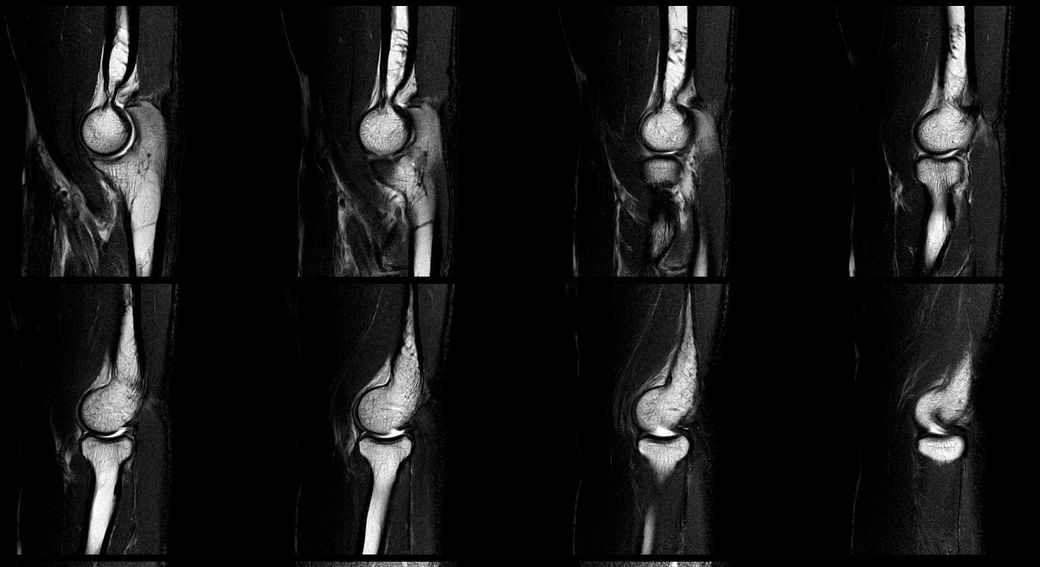

검사 결과 (7월 중순)

- MRI: 좌측 삼두건 경미한 염증, ulnar nerve supracondylar level 경미한 신호 증가

- 초음파/근전도: 척골신경 아탈구 확인

아래는 관련 사진 첨부합니다.

• 3번 째 사진